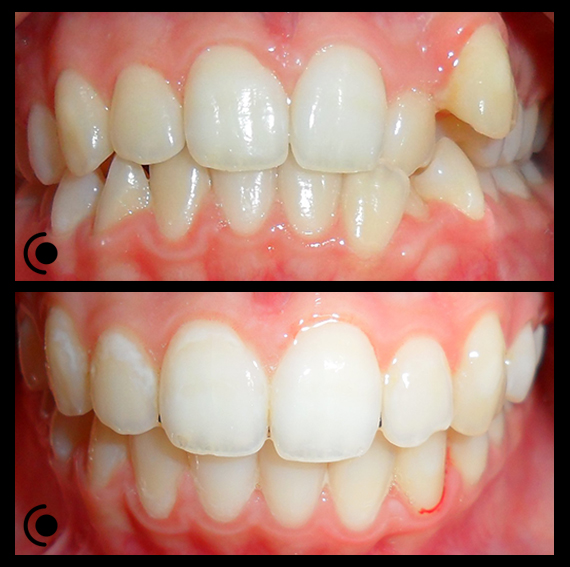

O našoj kvaliteti najbolje govore naši rezultati!

Centar za ortodonciju Petra Džapo